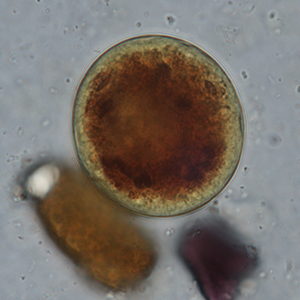

Le kyste est sphérique à ovoïde, à paroi épaisse, mesurant 50 à 100 μm de diamètre. Il présente un contenu granuleux, un macronucléus et micronucléus difficilement visibles (Strait et al., 2012). La coloration au Lugol permet de mettre en évidence certains organites qui apparaissent en brun sombre, de colorer la paroi en brun et l’intérieur du kyste en jaune.